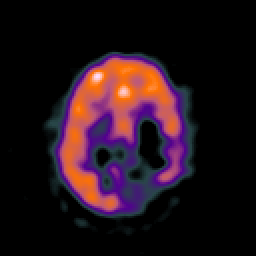

SPECT TC Study #8 -- Slice #37

[Home][Help][Clinical][Tour 1][Tour 2][Tour 3] Slice 37